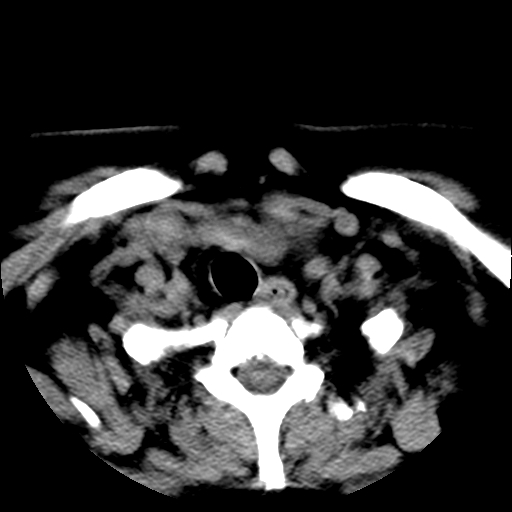

标题: CT25491:女,55岁,发现左侧甲状腺肿块一个月。 [打印本页]

标题: CT25491:女,55岁,发现左侧甲状腺肿块一个月。

女,55岁,发现左侧甲状腺肿块一个月,彩超示:甲状腺多发结节伴左叶结节液化。

腺瘤囊变

考虑左侧甲状腺腺瘤囊变。